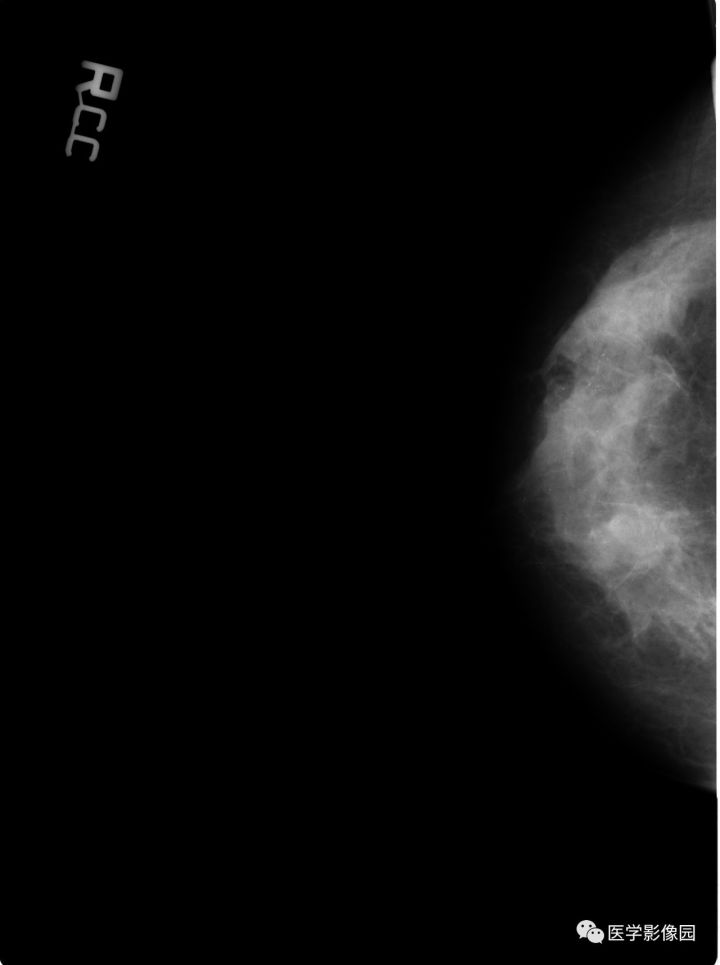

【病例】乳腺错构瘤1例X线钼靶

影像学表现:右乳近乳头处皮下卵圆形低密度影,边界清晰,其中可见多发小结节状高密度影,边界清晰。低密度影内尚可见少许斑点状钙化。

诊断结果:乳腺错构瘤